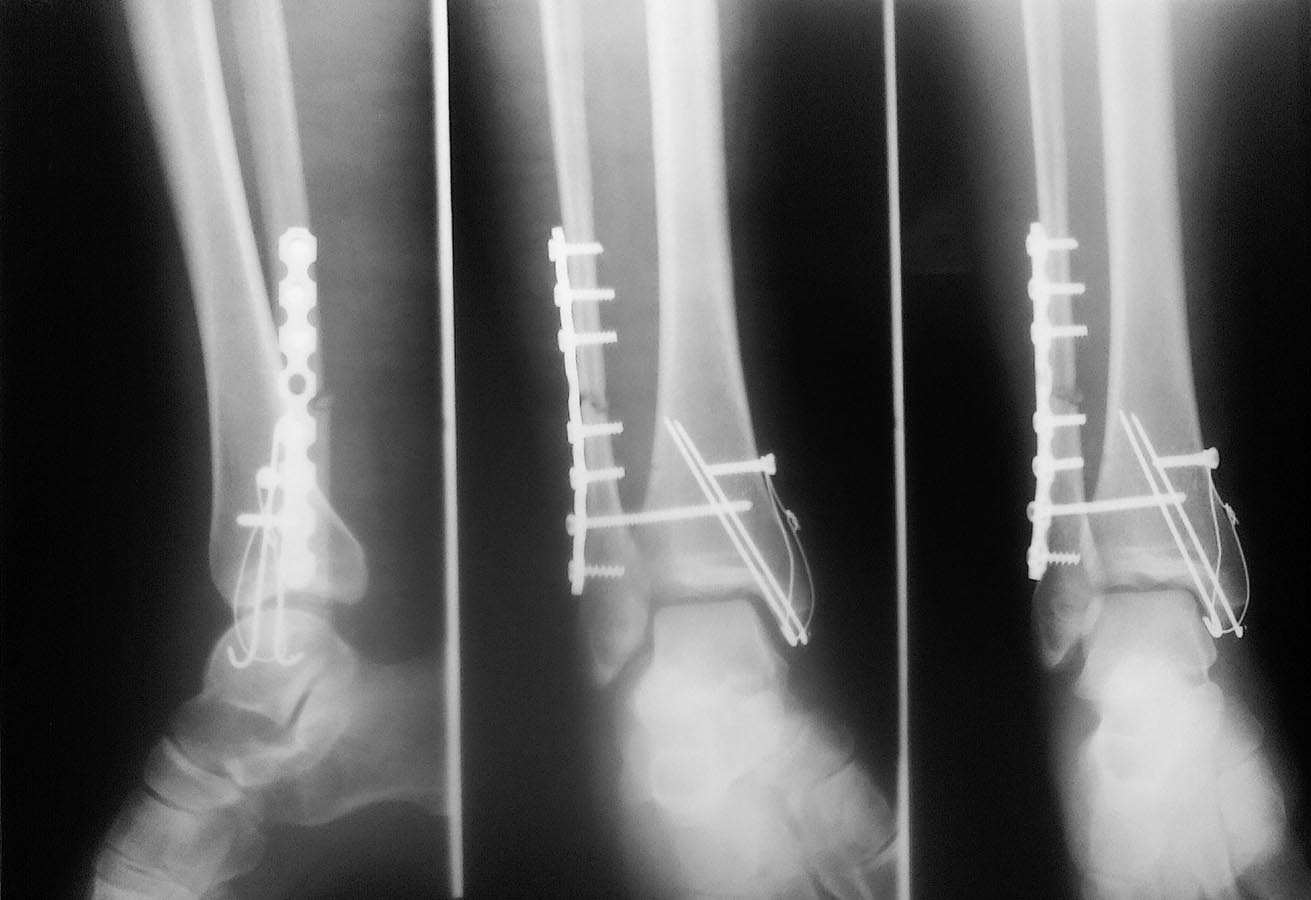

Уважаемые коллеги. Пациентка, 34 года получила травму в результате ДТП 06.08.2016. Перелом лодыжек 44С. Оперирована 12.08.2016.

Остеосинтез "правильный" в плане техники установки фиксаторов, но вот только репозиции нет. Так оставлять конечно нельзя. Возможно удастся удалить позиционный винт репонировать и переустановить винт, хотя не факт что удастся этим обойтись, не исключена интерпозиция.

А вот еще только рассмотрел - ось малоберцовой нарушера - загнута кпереди, скорее всего в этом причина, так что репозиция и реостеосинтез малоберцовой. Не оставляйте так - 34 года человеку всего то.

Нужно переделать, и чем быстрее - тем лучше.

Проблема в отсутствии репозиции малоберцовой кости - её угловом смещении. Всё остальное - следствие

Уважаемые коллеги. Получается, что из-за углового смещения дистальный отломок м/берцовой кости не анатомично попал в вырезку ББК(в ДМБС)в следствие чего и наблюдается передний подвывих? Прошу прощения за качество снимков.

По моему мнению на снимке в Мортисе длина м/берцовой кости востановлена (субхондральные пластинки совпадают), единственное что неравномерность суставной щели(может из-за неправильной укладки?).

"Уважаемые коллеги. Получается, что из-за углового смещения дистальный отломок м/берцовой кости не анатомично попал в вырезку ББК(в ДМБС)в следствие чего и наблюдается передний подвывих?"

Да именно так и не иначе. Но время пока есть и сейчас довольно просто будет все исправить.

У меня была похожая ситуация при данном переломе: подвывывих стопы кпереди после аналогичного МОС. Я взял пациента на операцию повторно. Переустановил пластину на малоберцовой кости, устранил угловое смещение (здесь также имеется антекурвация малоберцовой кости). Моя попытка установить позиционный винт приводил к появлению подвывиха стопы либо кпереди либо кзади. В итоге я не стал ставить позиционный винт, а для предупреждения подвывиха стопы кнаружи и стабилизации сустава провел 2 трансартикулярные спицы через пяточную кость